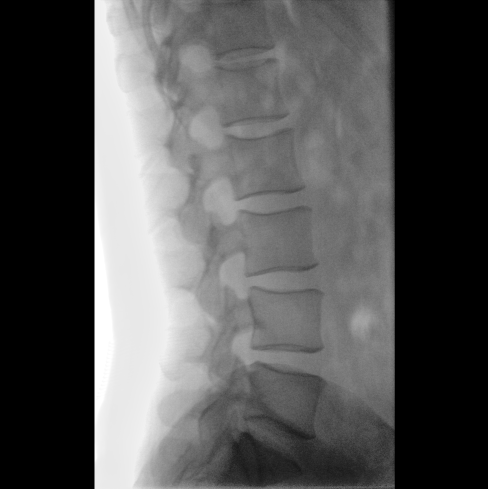

臨床應用廣泛,適用于關節(jié)手術、創(chuàng)傷手術、脊柱手術、疼痛治療等。

圖像清晰細膩

高清像素,低信噪比,細小的組織結構也可以清晰顯示。

Clinical picture

臨床圖片